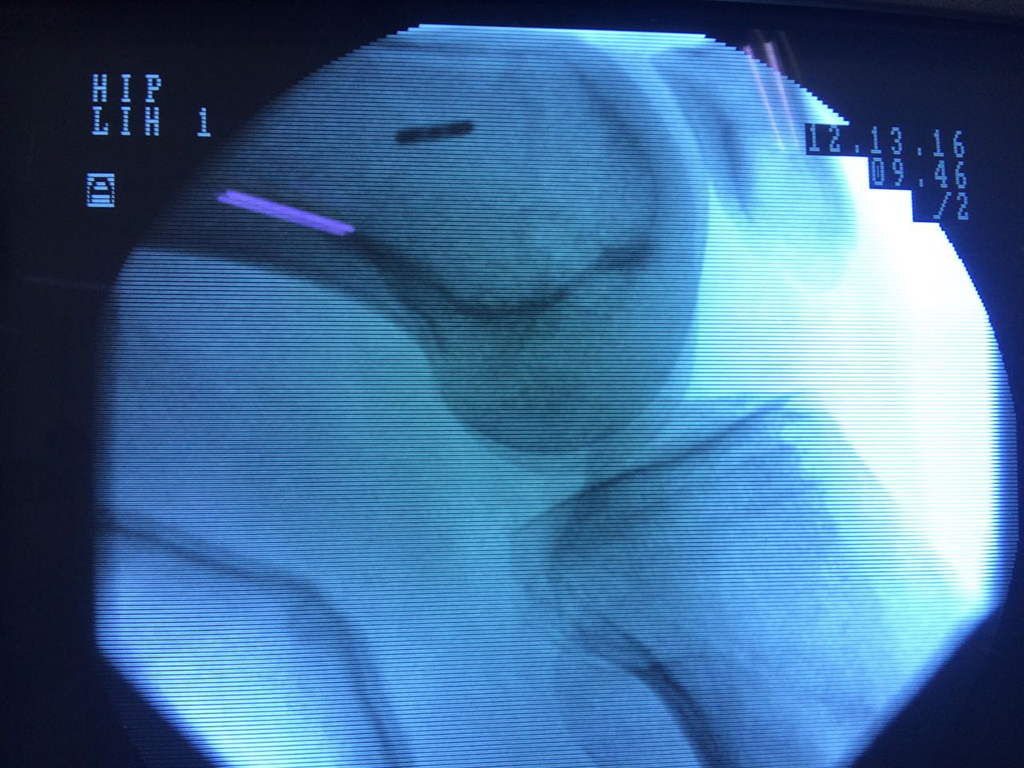

Cirugía de Cadera

La artroscopia de rodilla es un cirugía en el cual la estructura interna de la articulación es examinada ya sea para realizar un diagnostico o para realizar un tratamiento, este procedimiento se realiza utilizando un instrumento parecido a un pequeño tubo llamado artroscopio.